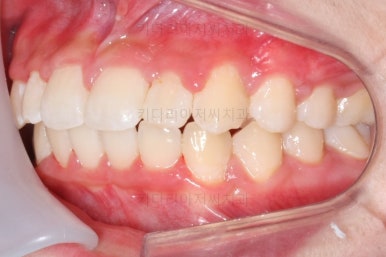

마찬가지로 부산교정치과 키다리아저씨치과에 처음 내원하셨을 당시의 입안 모습입니다.

화살표로 표시된 치아가 작은 앞니 부분인데 크기가 매우 작고 뾰족한 것을 볼 수 있어요. 유치가 아니고 평생 써야 하는 영구치입니다. 이러한 상태를 "왜소치"라고 표현하는데, 치아 크기의 문제로 여러 가지 문제점이 생길 수 있어요.

윗니 치아 사이에 틈이 생길 수 있습니다.(치아 크기가 모자란 만큼 틈이 있는 것이죠.)

아래 앞니가 삐뚤어질 수 있습니다.(비율상 아랫니가 상대적으로 커지기 때문에 삐뚤어지게 됩니다.)

미적으로 좋지 못합니다.

또 다른 문제는 위아래 앞니가 매우 많이 겹쳐져 있어서 아래 앞니가 거의 보이지 않는다는 점입니다.

그 다음 문제는 왼쪽 송곳니 부분(붉은색 동그라미)이 유치가 남아있고, 영구치가 매복되어 있는 경우였어요.